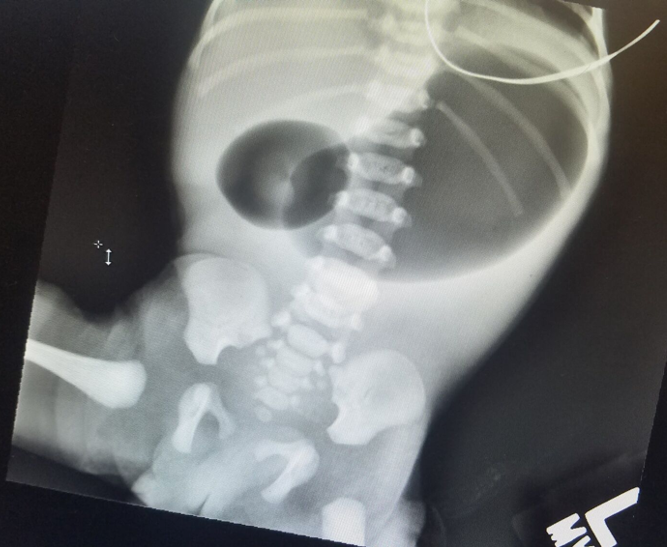

A boy was born via normal spontaneous vaginal delivery at 36 weeks and 1 day of gestation to a 20-year-old, gravida 1, para 1 woman. At 9 hours of life, a neonate presented with a large emesis, this time...